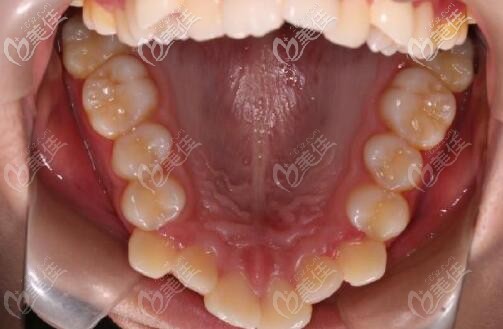

矯正前,牙齒有點(diǎn)錯(cuò)亂